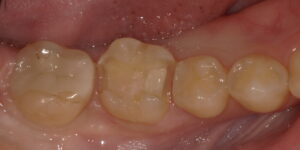

術中:セラミックを除去しました。虫歯は認められなかったため、セラミックの下に裏層されていたレジンはそのままにして、上部のみ充填することにしました。